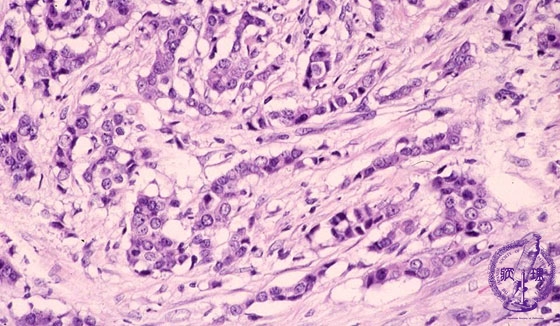

- 14.Breast

- š(6)Invasive ductal carcinoma(Scirrhous carcinoma)

Microscopic image(HE stain, high power view):Marked tumor infiltration has evoked reactive stromal fibrosis. This cancer termed gscirrhoush cancer and is classified as a poorly differentiated ductal carcinoma. Infilatration of small nests and cords of carcinoma cells is also observed.